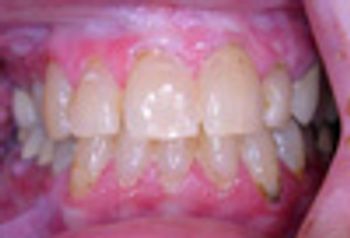

A 52-year-old woman presents with severe intra-oral ulceration and oral pain. She reports that several years earlier, she had been taking cephalexin when severe intra-oral ulceration developed.